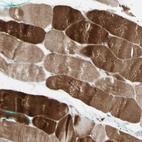

Immunohistochemical staining of human skeletal muscle shows strong cytoplasmic positivity in myocytes.